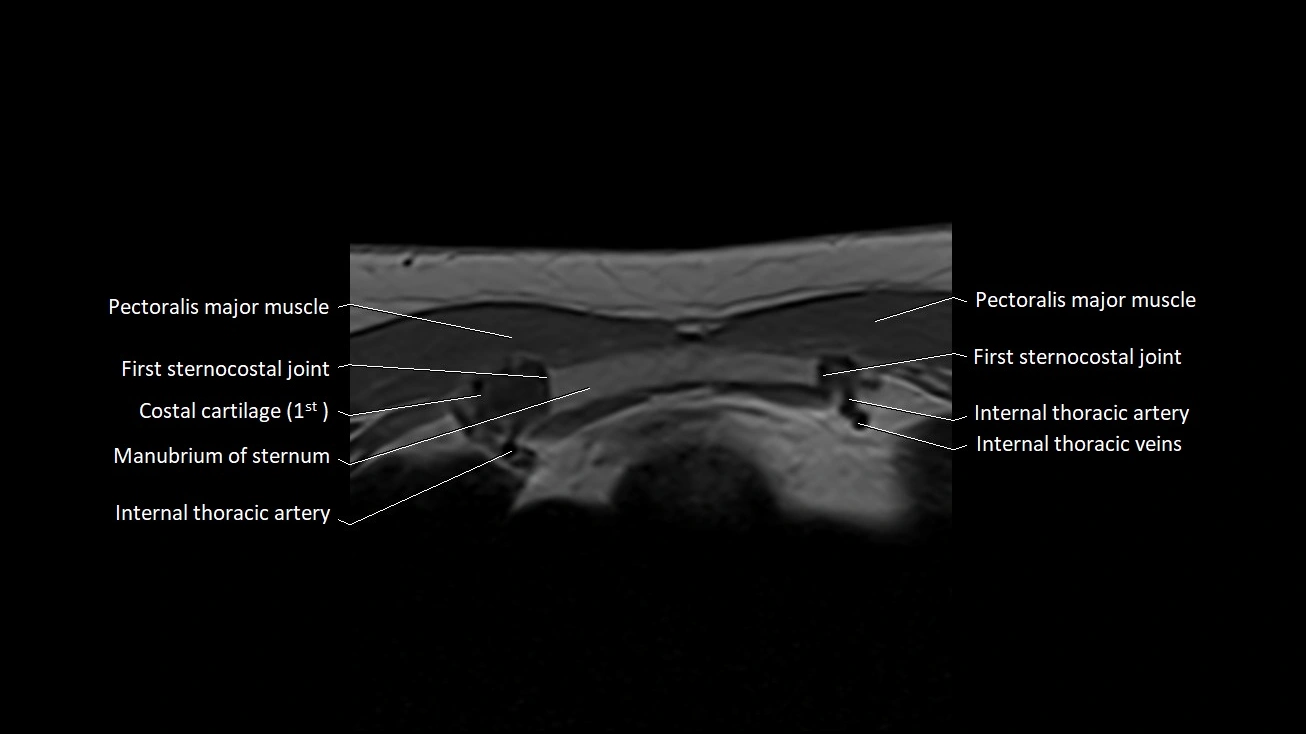

MRI images

image